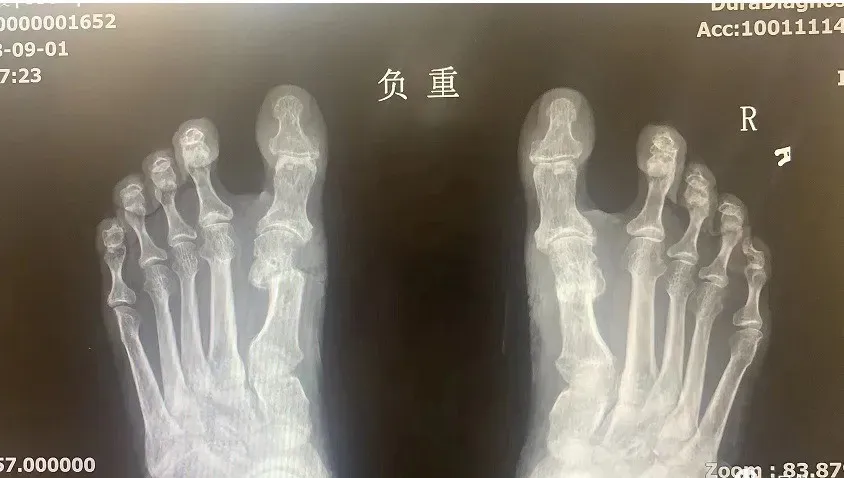

术后X光片参考